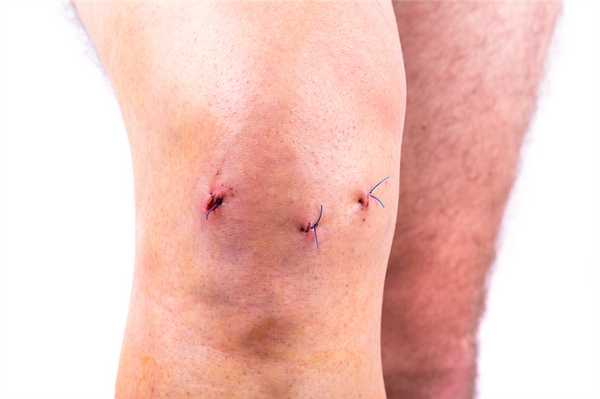

Когда еще не сняты швы.

По окончании операции физиологический раствор выводится из сустава, разрезы зашивают. Раны обрабатывают антисептиками и накладывают стерильный бинтовой бандаж. Процедура отнимает от 30 до 60 минут.

Сначала ногу пациента сгибают и через небольшой разрез вводят канюлю. Затем — разгибают и через канюлю вводят артроскоп. Инструменты для артроскопических манипуляций вводят через небольшие разрезы длиной 4-5 мм. После операции артроскоп и все инструменты извлекают, а послеоперационные раны зашивают и заклеивают лейкопластырем.